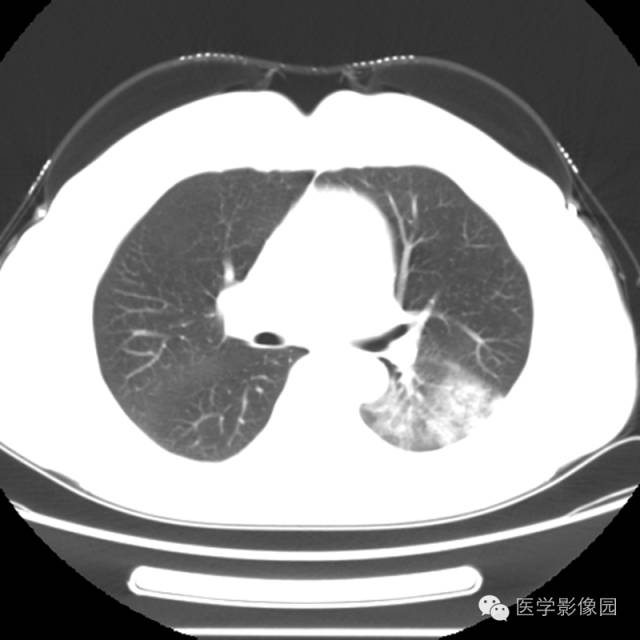

肺叶实变性支气管肺泡癌1例CT影像表现